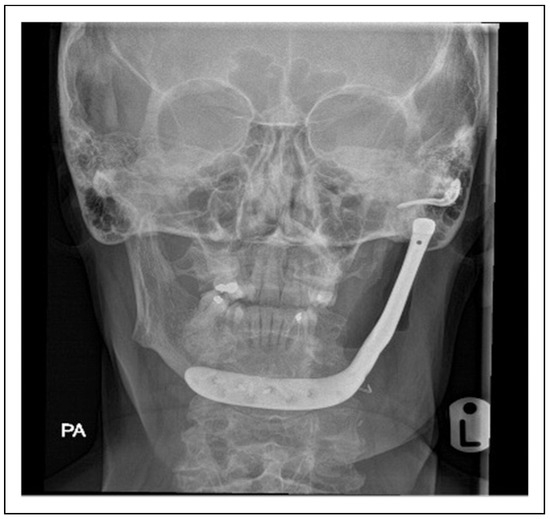

Bilateral TMJ Replacement With Complete Replacement of the Mandible, Patient 8